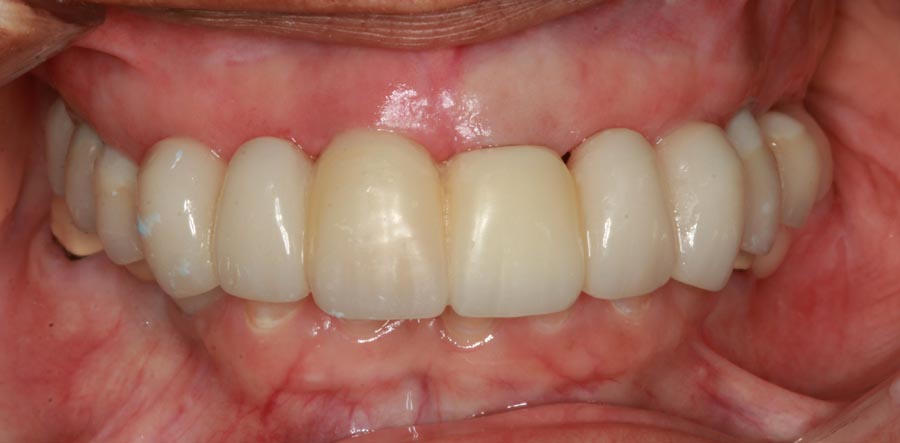

Smile GalleryImplant RestorationsFull Mouth Implant Restoration Full arch zirconia implant bridge (full smile) 1 of 37 Pre-op full smile Pre-op lips retracted Pre-op panoramic x-ray Extraction of strategic teeth Placement of implants Extraction of some remaining teeth after verification of adequate implant stability Occlusal view Post-op panoramic x-ray Immediately fabricated provisional restoration (tissue side view) Immediately fabricated provisional restoration (occlusal side view) Immediate provisional delivered on day of surgery Immediate provisional 2 weeks later Scalloped tissue developed from the provisional at 2 weeks Jig used for making a master impression Provisional in place (full smile) Provisional in place (lips retracted) Provisional in place (right side) Provisional in place (left side) Wax try-in (full smile) Wax try-in (right side full smile) Wax try-in (left side full smile) Wax try-in (full face, lips together) Wax try-in (full smile) Wax try-in (right side) Wax try-in (left side) Wax try-in (lips retracted) Full arch zirconia implant bridge on master cast (frontal view) Full arch zirconia implant bridge on master cast (occlusal view) Implant positions and soft tissue representation on master cast (occlusal view) Soft tissue representation on master cast (frontal view) Full arch zirconia implant bridge (tissue side view) Soft tissues on day of delivery (occlusal view) Soft tissues on day of delivery (frontal view) Full arch zirconia implant bridge delivered (lips retracted) Full arch zirconia implant bridge (lips retracted, close up) Post treatment panoramic x-ray Full arch zirconia implant bridge (full smile)